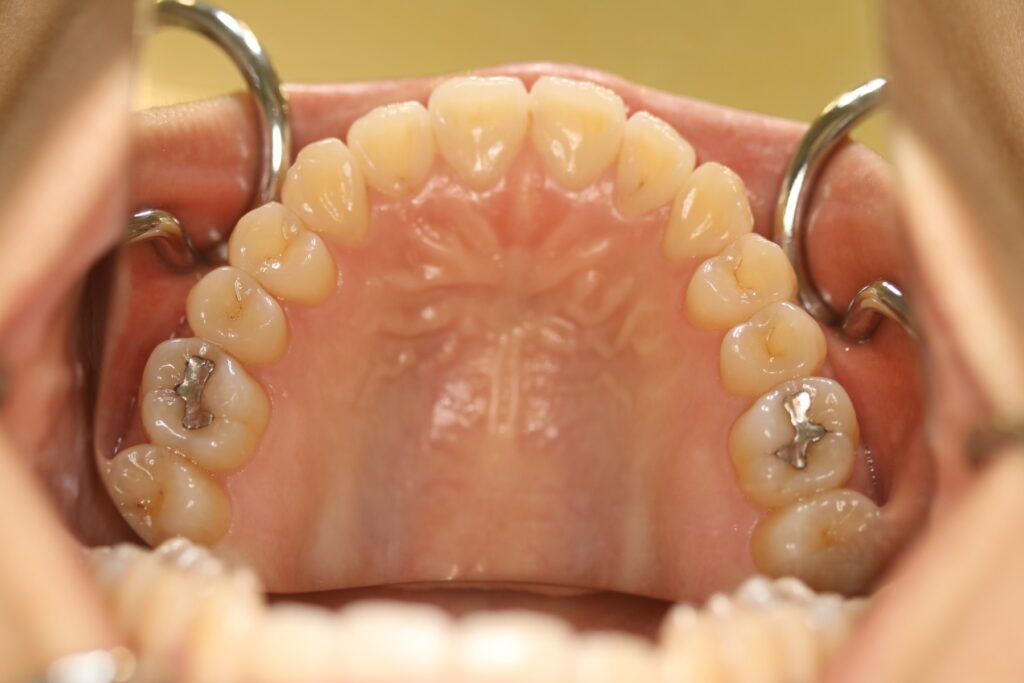

治療実績(症例) アライナー矯正 症例1 上顎前突症例 症例2 上下顎前突症例 症例3 叢生 症例4 開咬 症例5 開咬(外科的矯正治療) アライナー矯正 Post Share Hatena Line RSS feedly Pin it note 1.主訴2.診断名3.初診時年齢4.治療に用いた主な装置とオプション5.抜歯部位6.治療期間・通院回数7.総額と費用内訳総額相談検査・診断料調整料4,000円8.リスク・副作用 治療前 治療中 治療後